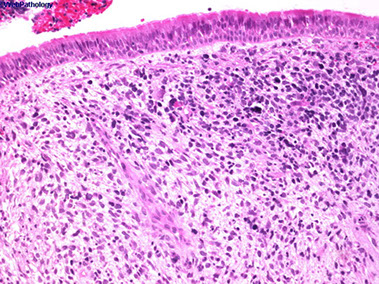

Rhinosporidiosis

most likely a fungal infx of URT 2/2 Rhinosporidium seeberi, seen in livestock and transmitted in water and dust

- M>F, endemic to South Asia, and South America

- sporadic in USA

- causes nasal obstruction

Micro: large (up to 300 um) sporangia in submucosa c lots of endospores

- may have thick sq mucosal epithelium, inc chronic inflam, not commonly granulomatous

DDx: coccidioidomycosis (sporangia are smaller), cylindrical cell papilloma

Tx: excision (no abx available for this organism)